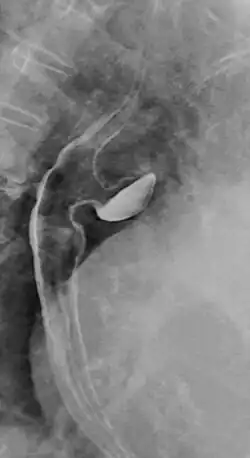

Ösophagusdivertikel

Das Ösophagusdivertikel und der Ösophaguspouch sind Ausstülpungen bzw. Erweiterungen (Divertikel) der Speiseröhre, die sich in unterschiedlichen Höhen derselben finden, unterschiedliche Ursachen und einen unterschiedlichen Krankheitswert haben. Man unterscheidet